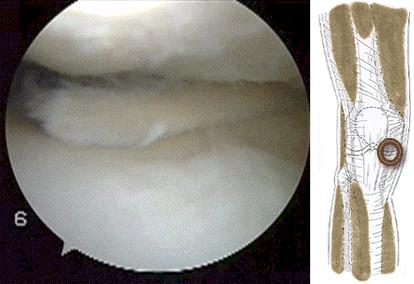

●E为瓣状裂 撕裂形成了一个活瓣,这种撕裂由于活动性比较大,而且撕裂,通常经过白区和红白区几乎没有愈合的可能。下图就是一个经典的半月板瓣状裂术中的影像学资料我们可以看到,由于这种撕裂没有及时处理,还把整个关节的软骨磨出了坑,这种情况将来非常容易出现骨关节炎。

半月板瓣状裂 导致关节内软骨磨损严重